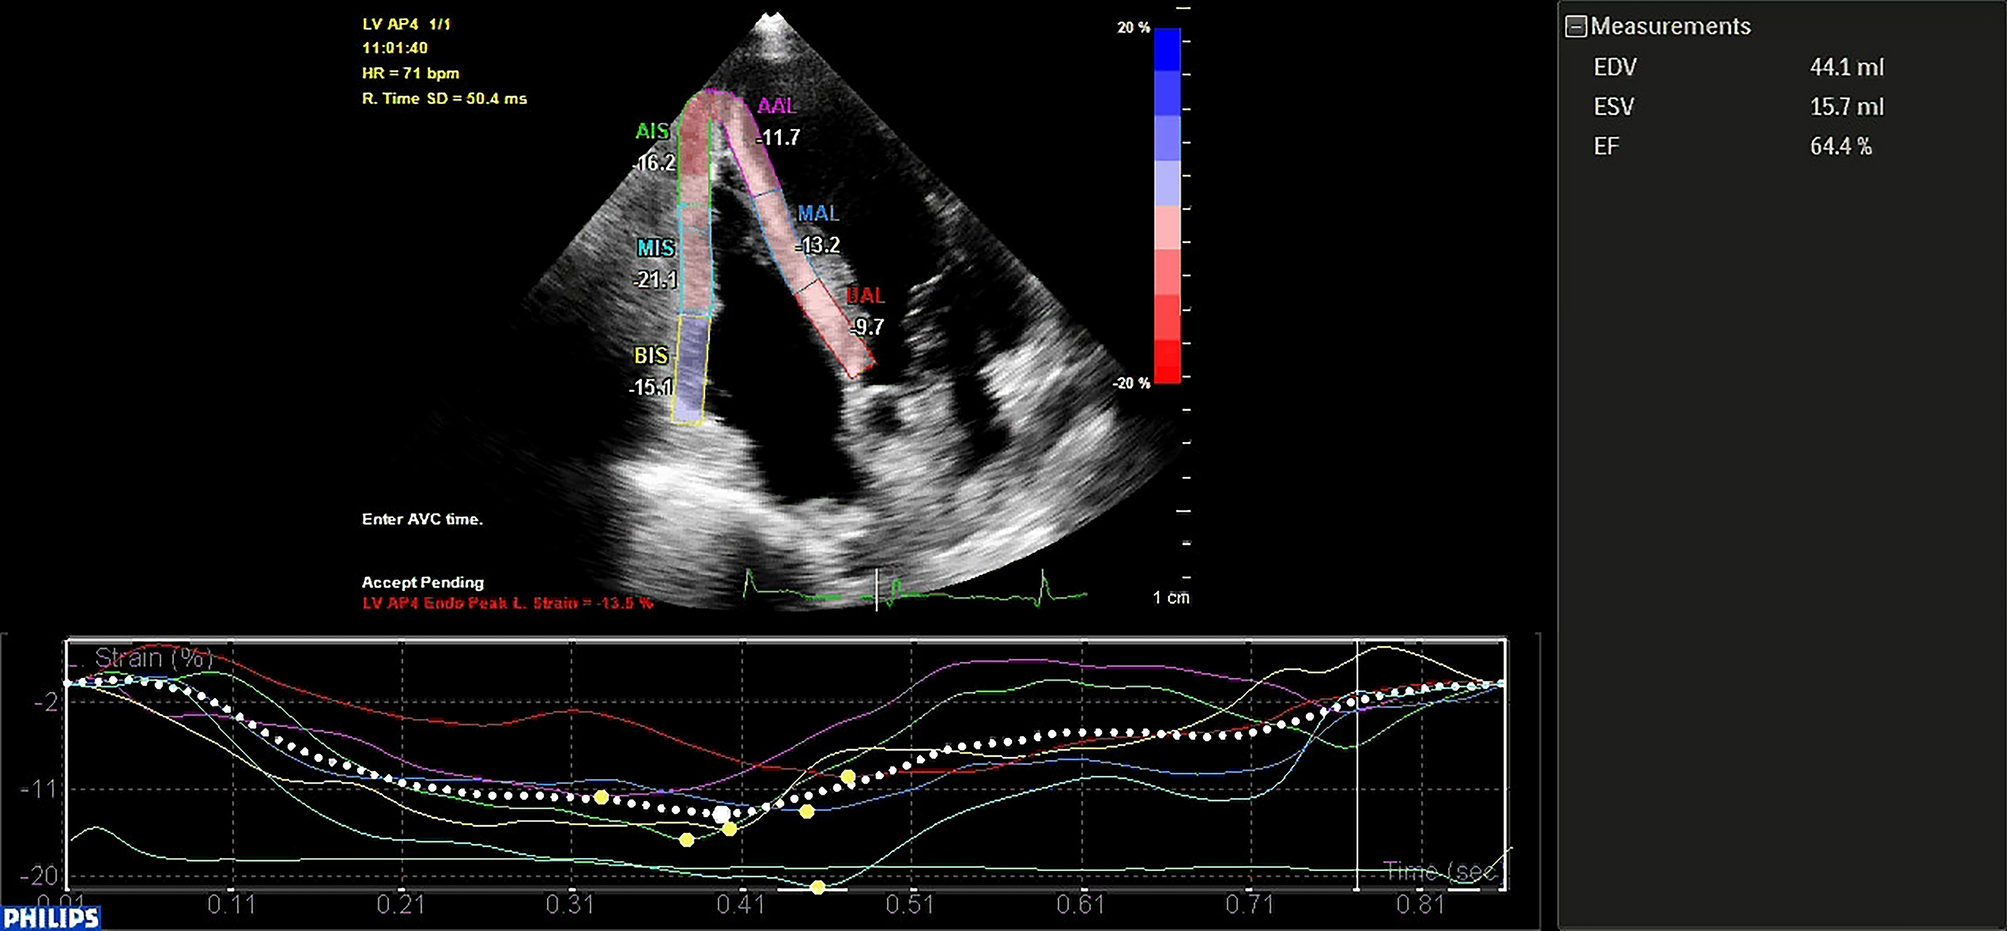

Figure 1

Speckle-tracking echocardiography analysis in an OSAS patient: the right ventricle is divided in 6 segments: 3 on the free wall and 3 in the septum.